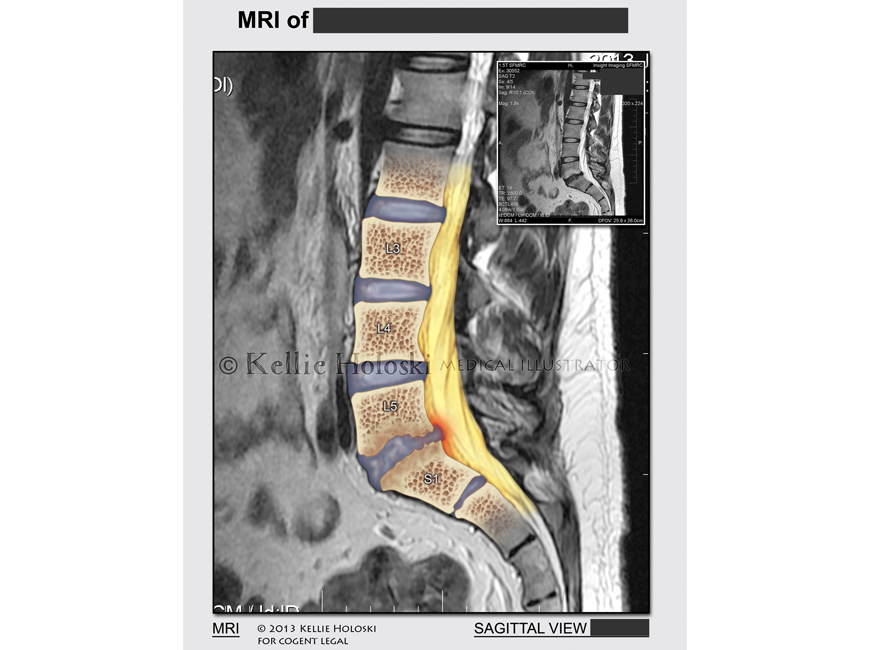

Herniated Disc L5, S1,

Adobe Photoshop

Courtroom exhibit for Cogent Legal;

©Kellie Holoski -